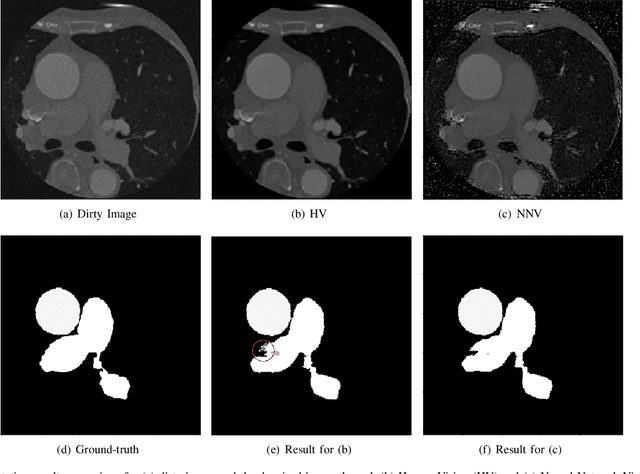

Abstract:Deep learning had already demonstrated its power in medical images, including denoising, classification, segmentation, etc. All these applications are proposed to automatically analyze medical images beforehand, which brings more information to radiologists during clinical assessment for accuracy improvement. Recently, many medical denoising methods had shown their significant artifact reduction result and noise removal both quantitatively and qualitatively. However, those existing methods are developed around human-vision, i.e., they are designed to minimize the noise effect that can be perceived by human eyes. In this paper, we introduce an application-guided denoising framework, which focuses on denoising for the following neural networks. In our experiments, we apply the proposed framework to different datasets, models, and use cases. Experimental results show that our proposed framework can achieve a better result than human-vision denoising network.

Abstract:CT image denoising can be treated as an image-to-image translation task where the goal is to learn the transform between a source domain $X$ (noisy images) and a target domain $Y$ (clean images). Recently, cycle-consistent adversarial denoising network (CCADN) has achieved state-of-the-art results by enforcing cycle-consistent loss without the need of paired training data. Our detailed analysis of CCADN raises a number of interesting questions. For example, if the noise is large leading to significant difference between domain $X$ and domain $Y$, can we bridge $X$ and $Y$ with an intermediate domain $Z$ such that both the denoising process between $X$ and $Z$ and that between $Z$ and $Y$ are easier to learn? As such intermediate domains lead to multiple cycles, how do we best enforce cycle-consistency? Driven by these questions, we propose a multi-cycle-consistent adversarial network (MCCAN) that builds intermediate domains and enforces both local and global cycle-consistency. The global cycle-consistency couples all generators together to model the whole denoising process, while the local cycle-consistency imposes effective supervision on the process between adjacent domains. Experiments show that both local and global cycle-consistency are important for the success of MCCAN, which outperforms the state-of-the-art.